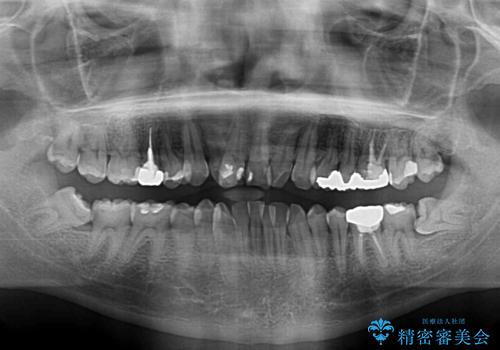

口元の突出感はないものの、上顎前歯のデコボコが著しかったため、上下顎左右小臼歯4本を抜歯することとしました。

上下の正中位置を改善するため、右下は第一小臼歯を、その他は第二小臼歯を抜歯することとしました。

第二小臼歯抜歯の矯正治療は、治療期間が長引くことが多いですが、動きが非常に良く、予定の治療期間で終えることができました。